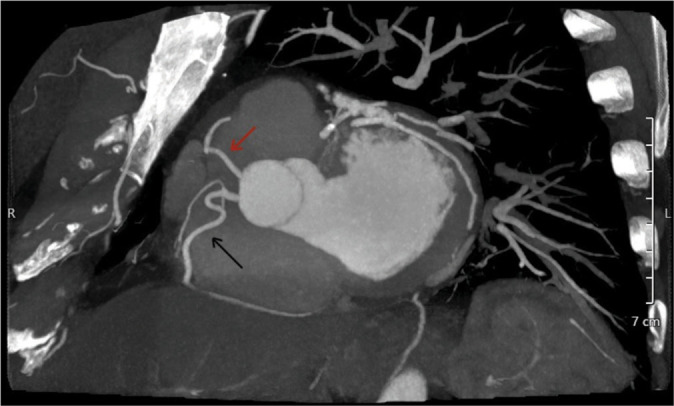

Dual left anterior descending (LAD) coronary artery is a rare anatomical variant with significant clinical implications. Recognizing this variant is crucial for accurate diagnosis and effective management, particularly in the context of revascularization strategies. We present a 71-year-old male with a history of dyspnea on exertion with baseline wall motion abnormality on a transthoracic stress echocardiography irreversible after exercise. Coronary computed tomography angiography revealed a dual LAD system: The left short LAD (LAD1) originating from the left main coronary artery and the right LAD (LAD2) arising separately from the right coronary cusp, distinct from the right coronary artery ostium. Having different origins and courses, both LADs supply the LAD territory. Our case is notable for two main reasons: The rarity of this particular type of dual LAD anatomy and the unique course of the LAD2, which, to our knowledge, has not been described in any previous case report. Although rare, dual LAD coronary artery should be considered in patients with atypical short LAD. Comprehensive imaging and a thorough understanding of coronary artery variants are essential for accurate diagnosis and effective management.

Abstract Image